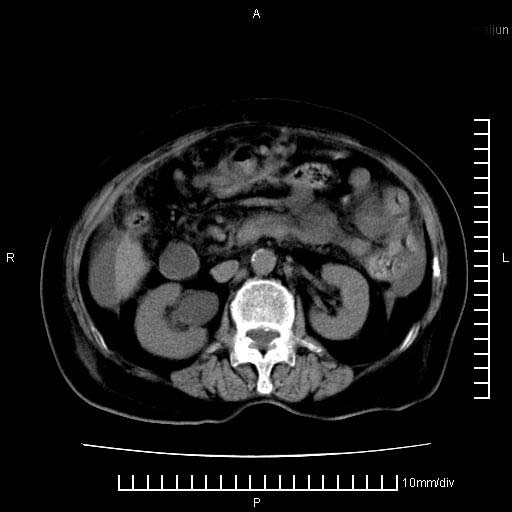

上腹疼痛月余,外院核磁诊断胰腺癌。现临床示右下腹可明显触及包块,可片子上怎么没有看到?

1.胰腺颈体部癌。

2。腹腔积液。

3。右胸腔积液,伴右肺下叶部分萎陷。

4。右肾盂囊肿。

胰腺体部癌累及周围器官,腹膜、粘连

1。胰腺ca伴腹膜腔转移

2。肝左叶低密度灶,考虑转移可能

胰腺结构模糊,胰尾部见囊性包块,周围脂肪密度增高,左肾前筋膜增厚,胸水、腹水。不符合胰腺ca伴腹膜腔转移。考虑胰腺炎伴假性囊肿形成、胸腹腔积液。

1、考虑胰腺癌伴腹膜腔转移,胸腹水。

2、肝脏转移可能。

3、右肾盂囊肿。

1)考虑胰腺癌并胰腺假性囊肿形成。2)肝内低密度灶,不排除转移。3)右肾盂积水。4)腹水。5)右侧胸腔积液并右肺下叶部分膨胀不全。

考虑胰腺ca伴腹膜腔转移、肝左叶转移、右肾积水。右胸腔积液。